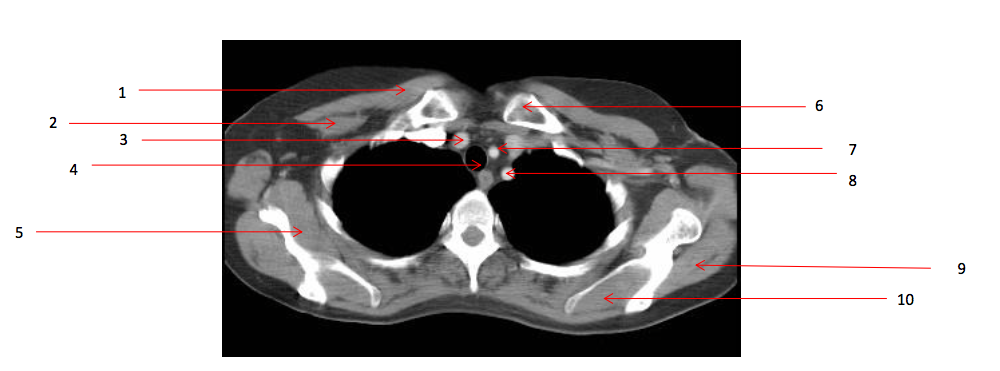

1

Number 2?

Rt pectoralis minor muscle

Q

Lt clavicle

Number 1?

Rt pectoralis major muscle

Number 8?

Lt subclavian artery

Trachea

Number 7?

Lt common carotid artery

Arch of aorta

Number 5?

Rt subscapularis muscle

Rt erectae spinae muscle

Number 9?

Lt infraspinatus muscle

Number 16?

Lt scapula

Number 14?

Lt brachiocephalic vein

SVC

Number 11?

Sternum (manubrium)

Number 18?

Number 12?

Rt brachiocephalic vein

Number 3?

Brachiocephalic artery

Number 15?

oesophagus